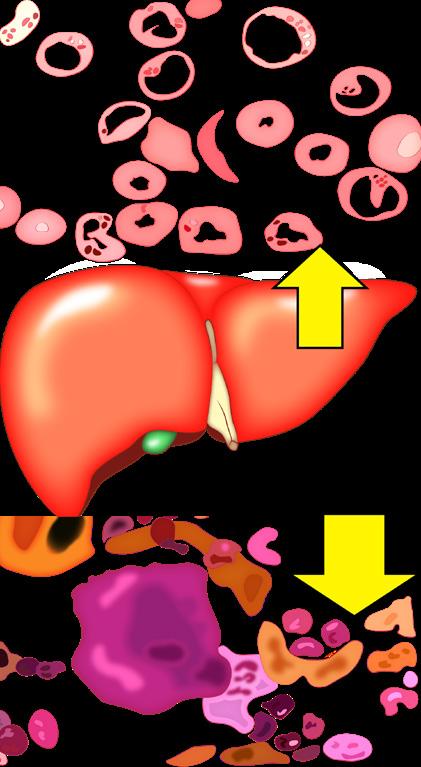

C. Sistema hematológico

Destaca la hemodilución fisiológica por el incremento del volumen plasmático (↑ 45 %), el cual diluye el aumento del volumen eritrocitario (↑ 33 %) de manera que se observa más plasma que eritrocitos . Predomina un estado protrombótico por aumento de los diferentes factores de coagulación, principalmente el fibrinógeno.